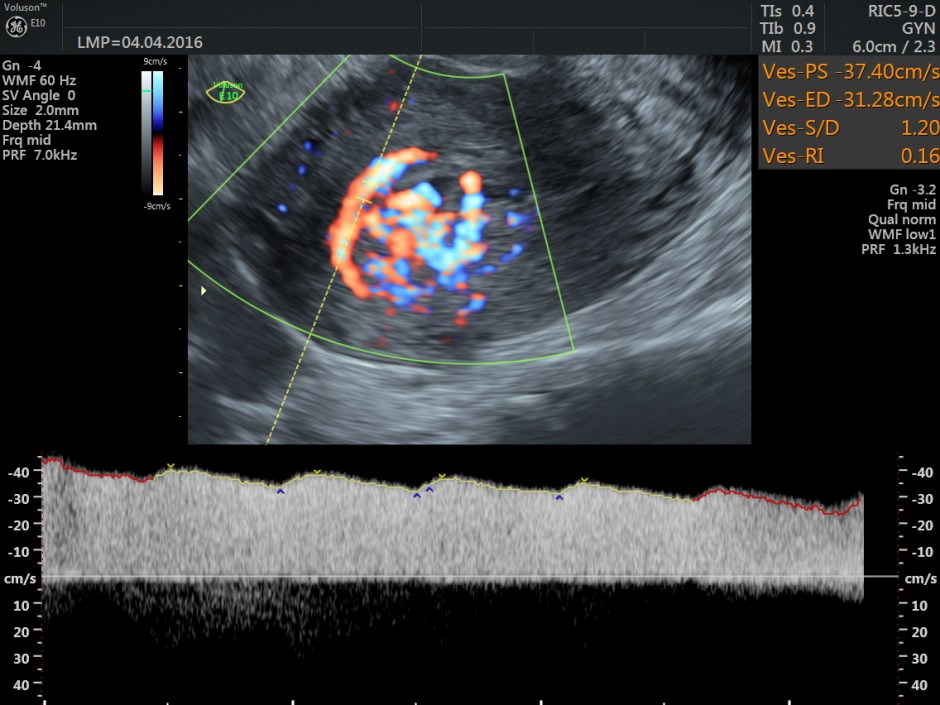

Spectral Doppler images show arterial flow with low resistance at different points .

The following are the different sections of the Power Doppler reconstruction images of the trans-vaginal scan.

Typically shows serpiginous/tubular anechoic structures within the myometrium with a low resistance (RI ~0.2-0.5), high velocity flow pattern on colour Doppler interrogation.